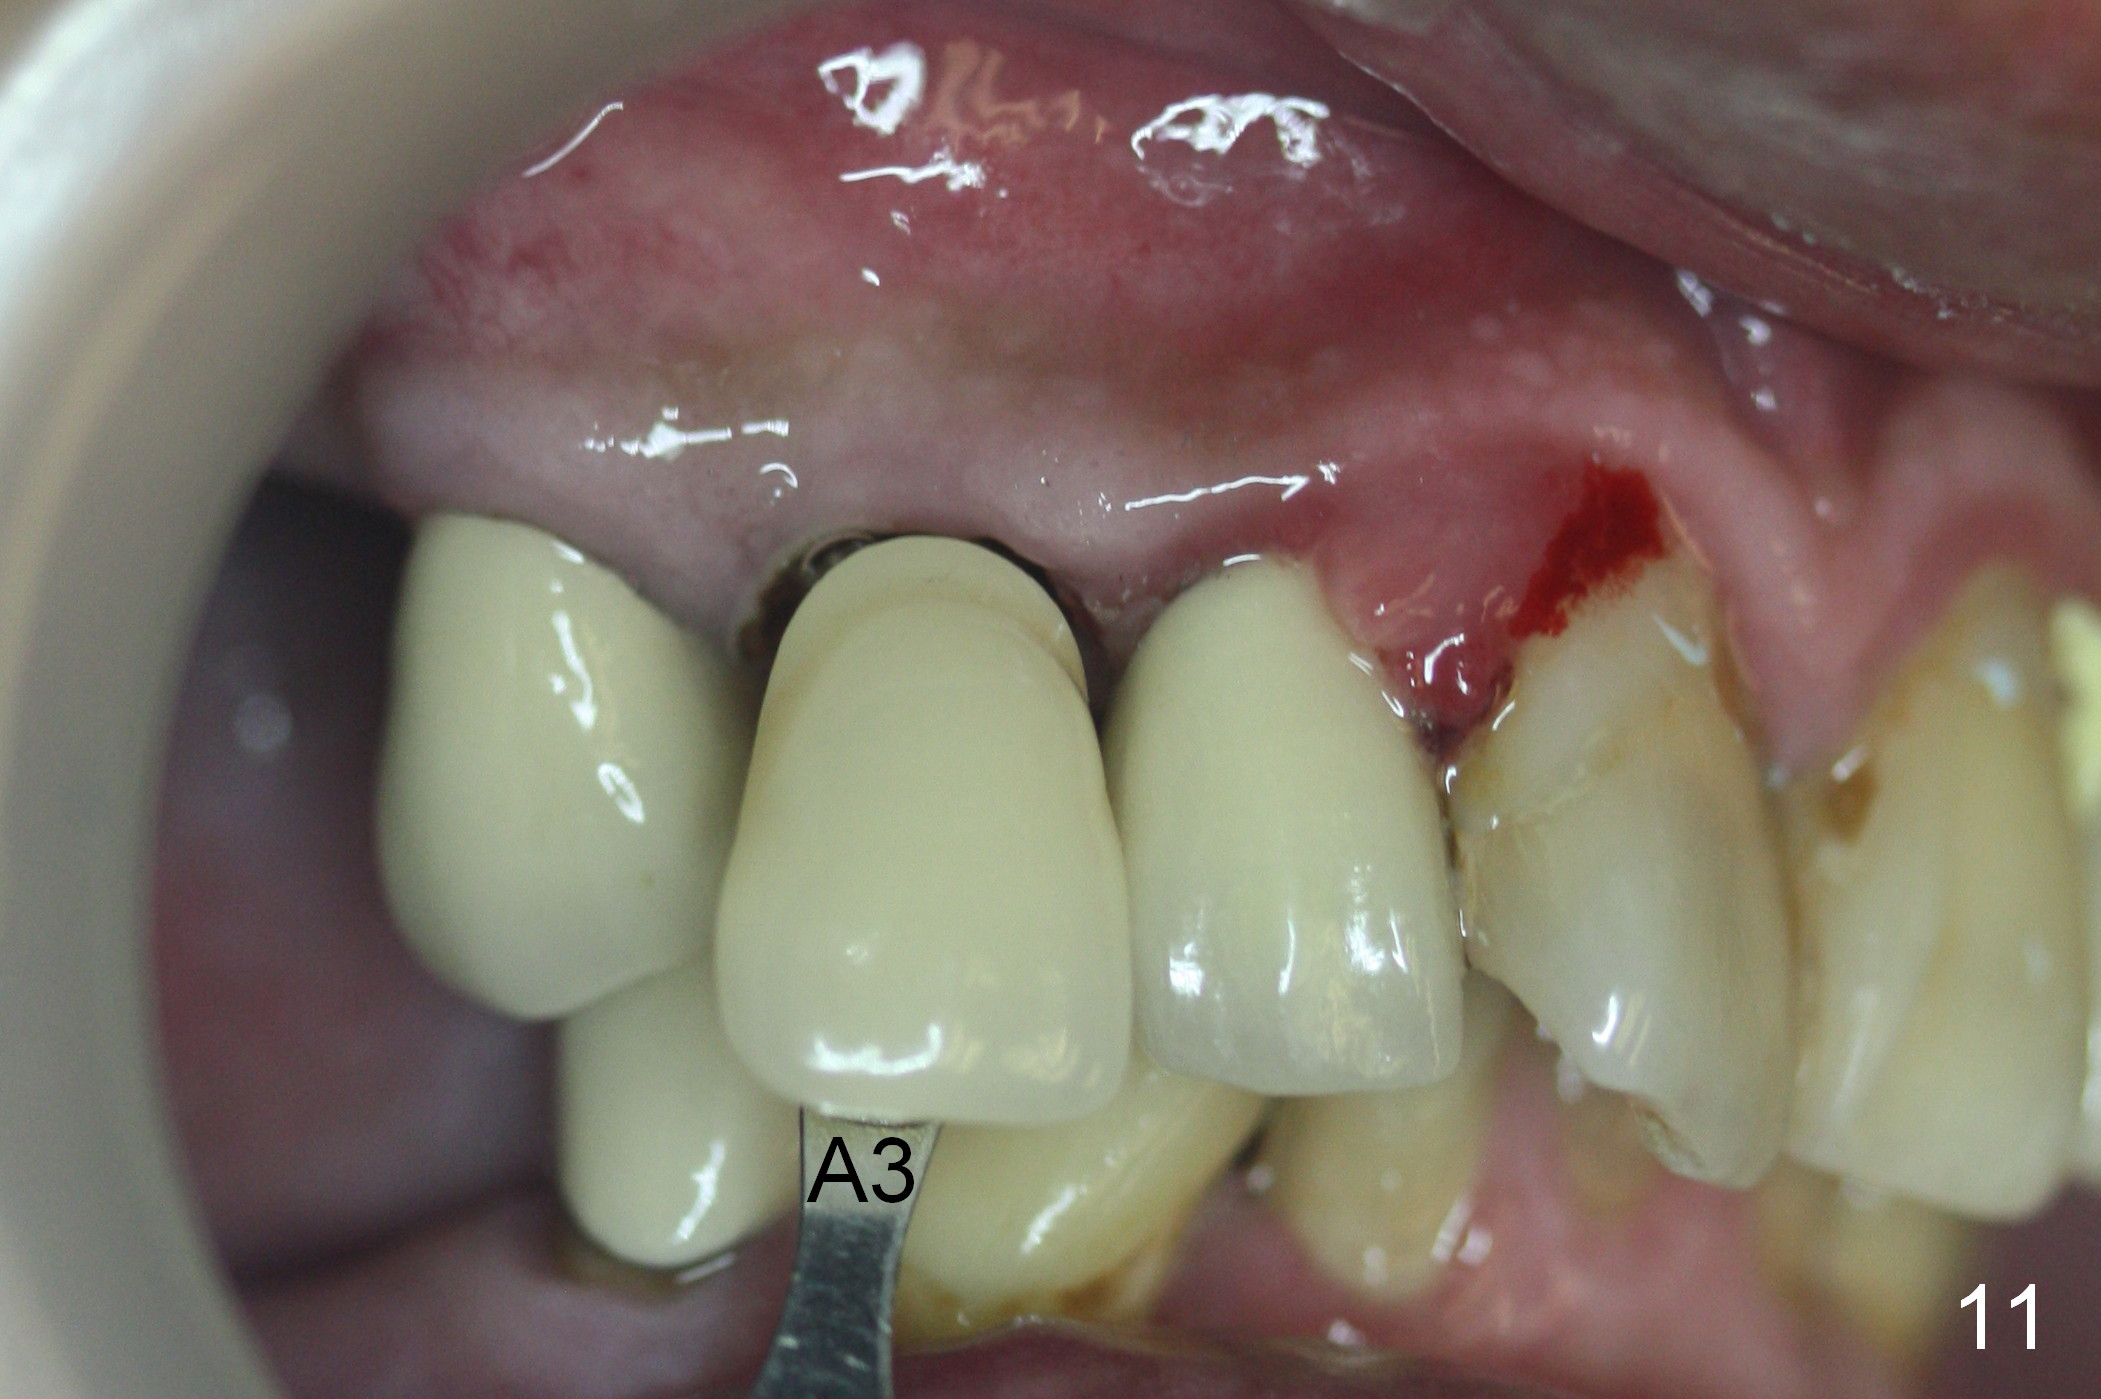

Six days post provisional reline, the mesial papilla erythema has subsided substantially; the abutment is changed to 4.5x5(2) with Diode gingivectomy (Fig.10-12).